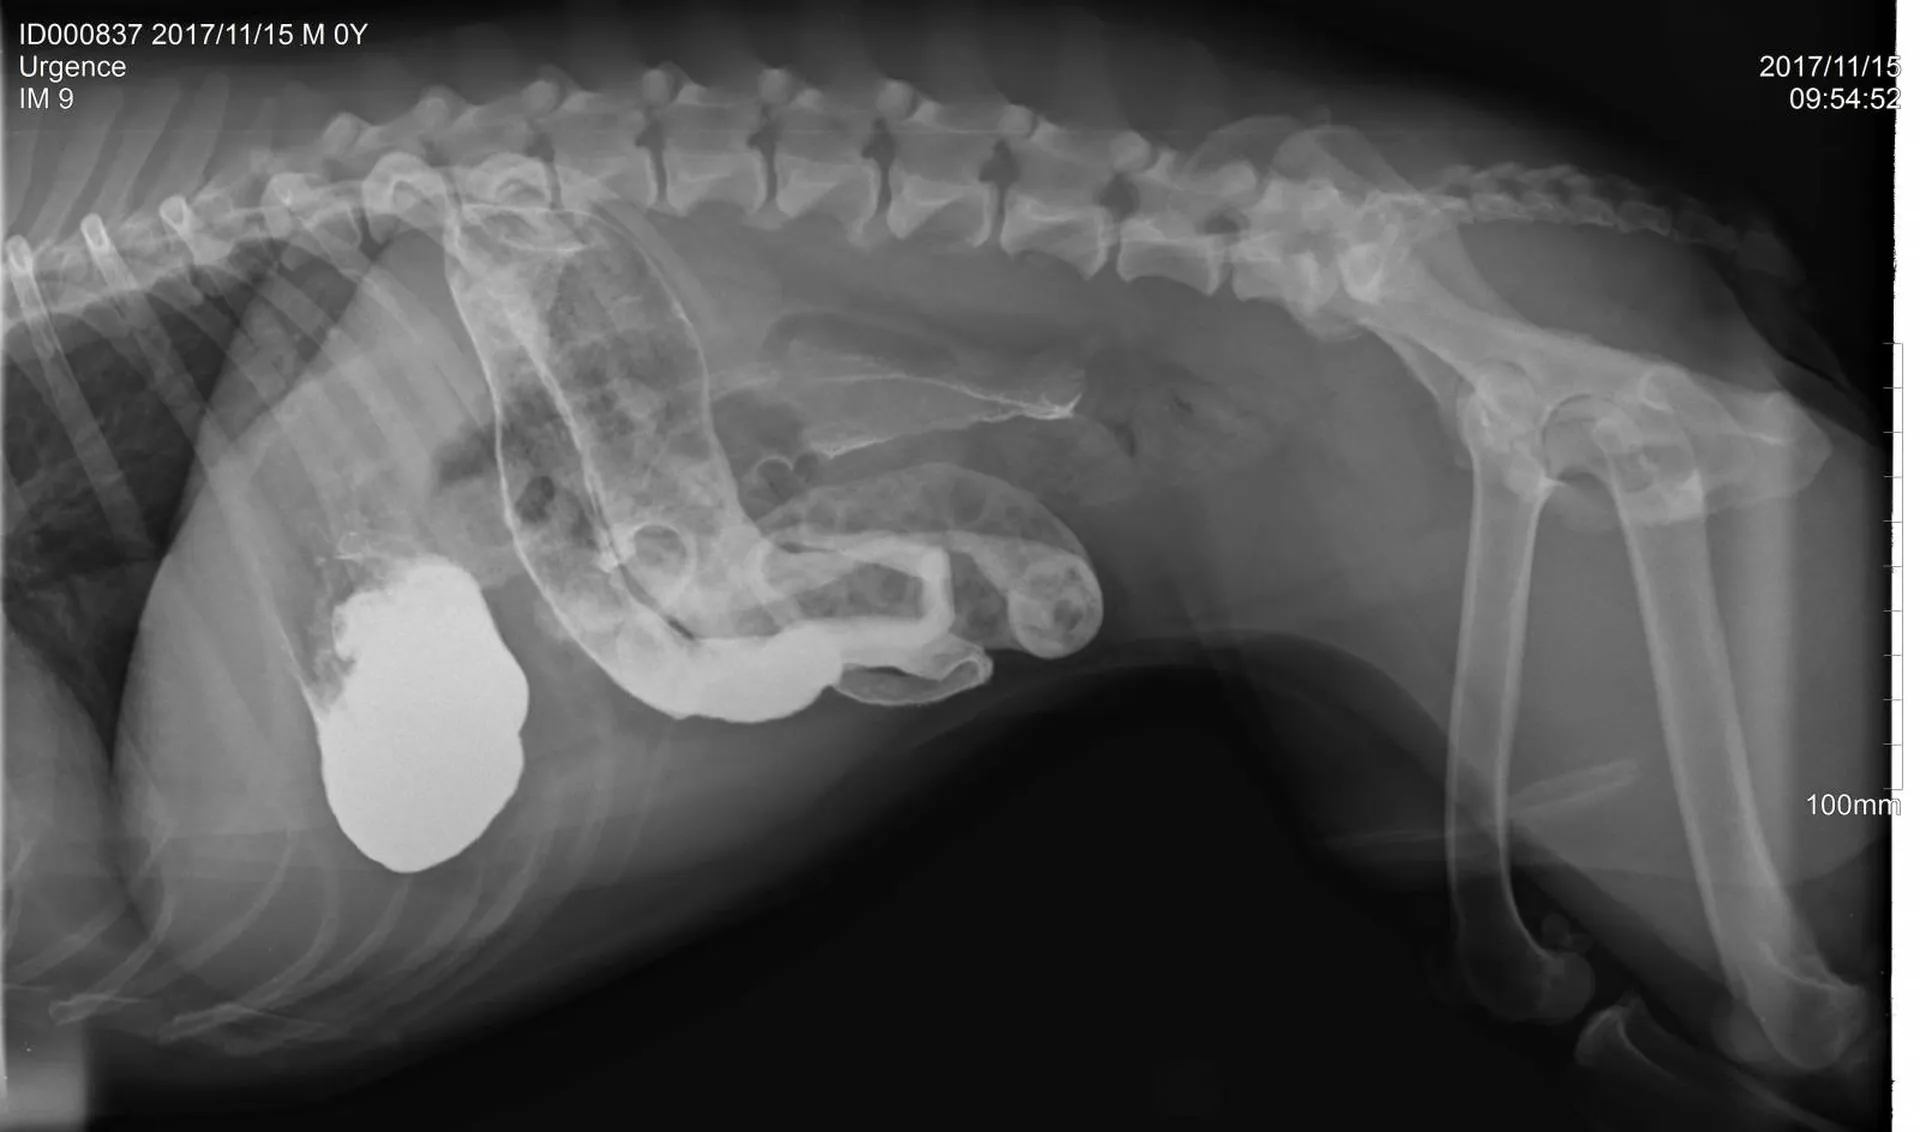

Une radiographie est un examen d’imagerie consistant à la prise de cliché au moyen d’un appareil à rayon X ceci afin de visualiser les différentes structures internes.

La radiographie reste indiquée dans de nombreuses affections, quelles soient respiratoires (radiographie cervicale ou thoracique), digestives (radiographie thoracique ou abdominale), locomotrices (membres, colonne), dentaires.

Votre chien, chat Nac est déposé sur la table de radiologie et différents clichés sont effectués dans différentes positions suivant la pathologie présentée.

Comme tout examen, il présente ses limites. Le principe de la radiographie étant l’utilisation du contraste (visualisation d’un tissu par rapport au tissu environnant et par rapport à sa radiodensité), certaines pathologies ne peuvent être que suspectées par radiographie mais nécessite d’autres examens (échographie, endoscopie, scanner, IRM).